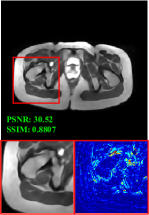

Figure 5 provides the qualitative comparison of the various methods on the four datasets at a scale of 4. The top, second, third, and bottom rows are the SR results under the FastMRI, clinical brain, clinical tumor and clinical pelvic datasets, respectively. The red boxes indicate the zoom-in region of complicated anatomical structures along with their corresponding error maps. Note that the brighter textures in the error maps, the lower the quality of the reconstructed images. As can be seen, compared to methods based on Transformers and CNNs, diffusion-based methods like DisC-Diff and DiffMSR (Ours) are capable of reconstructing high-realistic images with promising reconstruction metric scores (PSNR and SSIM). Nevertheless, while DisC-Diff can reconstruct high-precision MR images, it does not preserve the structure present in the original HR images, introducing some additional information that can affect medical diagnosis. In contrast, our method combines DM and PLWformer, which can preserve the original image’s structure while restoring high-frequency information.

| Method | Window Size | PSNR | SSIM | FLOPs |

| SwinIR [21] | 88 | 30.13 | 0.8107 | 32.99G |

| SwinIR [21] | 1616 | 30.54 | 0.8183 | 39.79G |

| PLWformer | 1616 | 30.52 | 0.8180 | 29.45G |

| PLWformer | 3232 | 30.78 | 0.8242 | 36.25G |

8 Window Size Analyses

We further show the comparison of window size and computational complexity (e.g., FLOPs) in Table 4. For a fair comparison, we conduct single-contrast SR reconstruction employing SwinIR [21] and PLWformer, with the optimization function utilizing the L1 loss. Note that in this case, the PLWformer does not utilize the prior knowledge represented by . The performance metrics, including PSNR, SSIM, and FLOPs, are evaluated with the image size set to 6464, the upsampling factor at 4, and using the FastMRI dataset. For SwinIR, expanding the window size can improve the performance of the network, but it also increases computational complexity. In contrast, PLWformer employs permutation operations to transfer some spatial information to the channel dimension. Therefore, even with an expanded window size, the computational complexity does not increase significantly. When the window size is 1616, the FLOPs required for PLWformer are smaller than those for SwinIR.

Besides, we observe that when the window size is the same, the performance of PLWformer is slightly lower than SwinIR, due to the reduction of tokens and in PLWformer, which leads to the loss of a small portion of the structural information of the image. However, PLWformer effectively reduces the computational burden, so a slight performance reduction is acceptable.